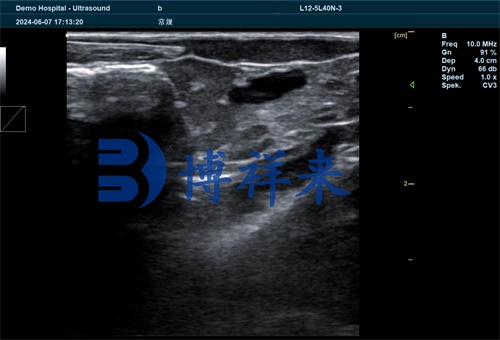

The fish ultrasound scanner operates using a high-frequency transducer that emits sound waves into the fish’s body. When these waves encounter tissues of varying densities, echoes are generated and captured by the probe. The scanner software converts these echoes into grayscale images, with varying brightness reflecting tissue boundaries, densities, and fluid content.

Ovarian Maturation Stage: The ultrasound image shows a mix of circular hypoechoic (dark) structures, representing developing oocytes, surrounded by hyperechoic (bright) connective tissue bands. Follicles appear as round or oval shapes of varying sizes.

Pre-parturition Stage: The image becomes more complex. Follicles are densely packed, with indistinct margins and the presence of anechoic (black) fluid regions indicating follicular fluid accumulation. This pattern signifies the fish is nearing ovulation or larval release.

Resting or Regressed Stage (Dry Period): The gonads appear flattened with uniformly echogenic textures, lacking distinguishable follicular structures. This indicates low reproductive activity, common during non-breeding seasons.